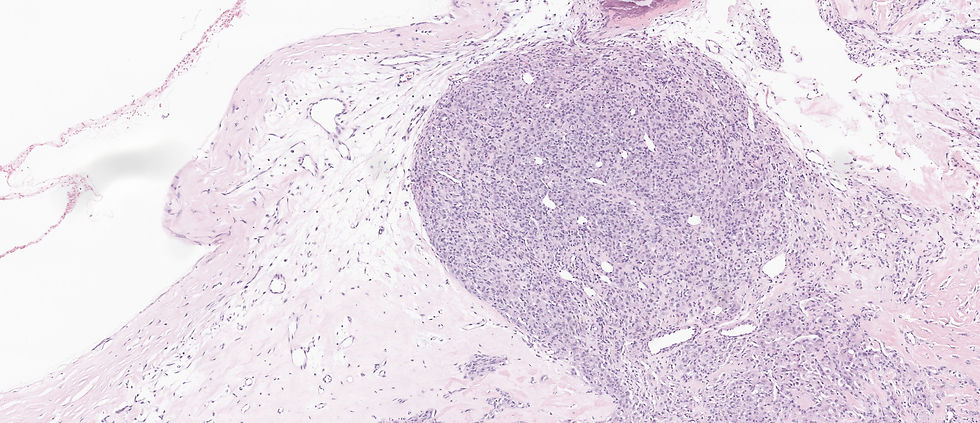

The correct answer is E. This is a classic case of sclerosing stromal tumor: 1) alternating cellularity 2) pseudo-lobular appearance 3) thin walled dilated staghorn vessels. The pseudolobules in a myxoid, edematous, or collagenous stroma is characteristic.